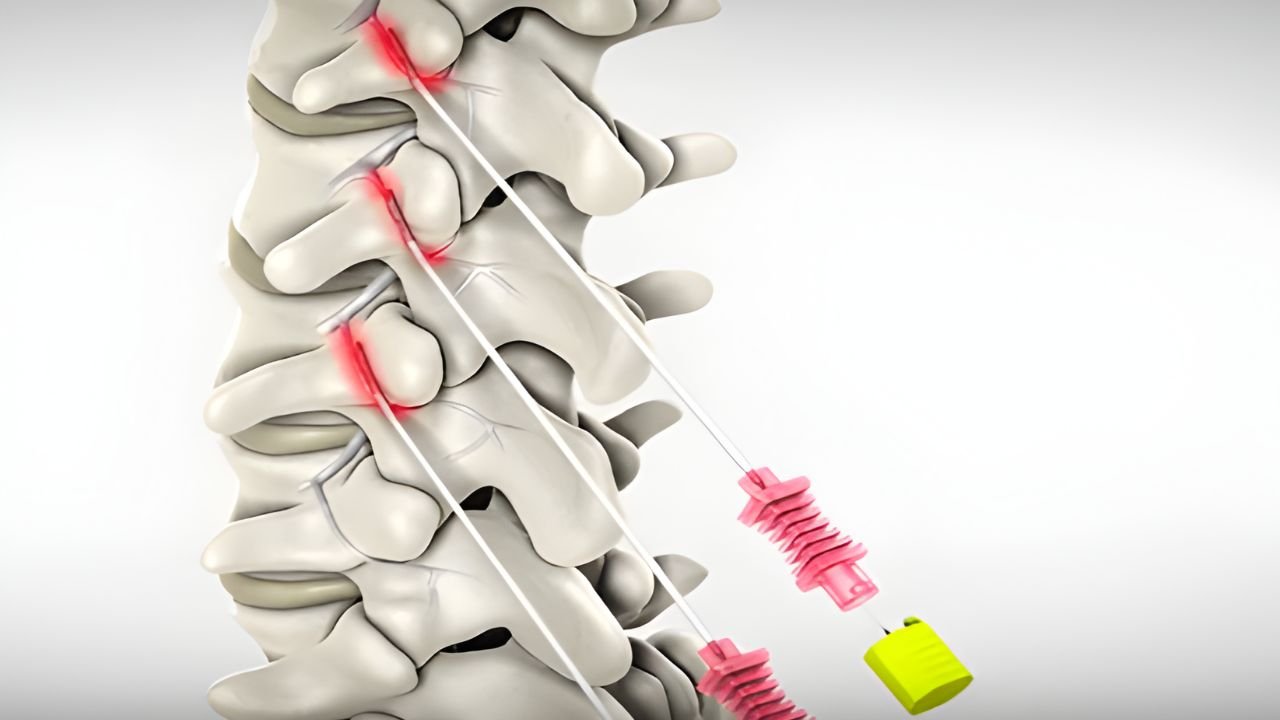

A dor crônica na coluna é frequentemente associada a hérnias de disco, mas uma causa muito comum e subdiagnosticada é

A dor crônica na coluna é frequentemente associada a hérnias de disco, mas uma causa muito comum e subdiagnosticada é

A dor crônica na coluna é frequentemente associada a hérnias de disco, mas uma causa muito comum e subdiagnosticada é

São técnicas onde utilizamos ultrassom ou radioscopia em

tempo real para guiar agulhas e instrumentos com precisão milimétrica até o alvo da dor. Isso garante maior segurança e eficácia.